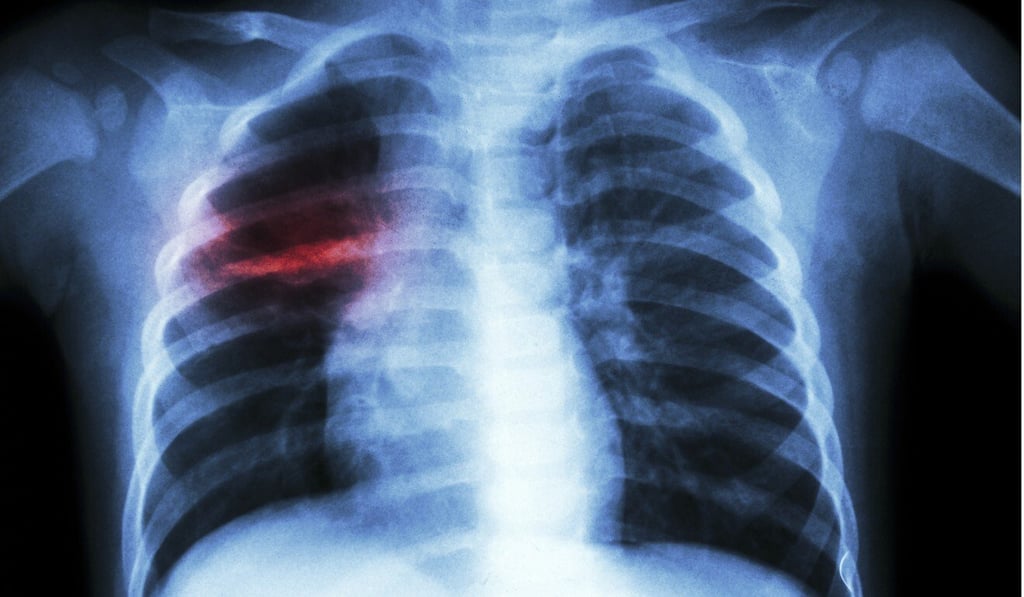

The World Health Organisation estimates that in 2018, some 10 million people fell ill with TB – a bacterial infection that usually attacks the lungs – and 1.5 million people died of the disease globally.